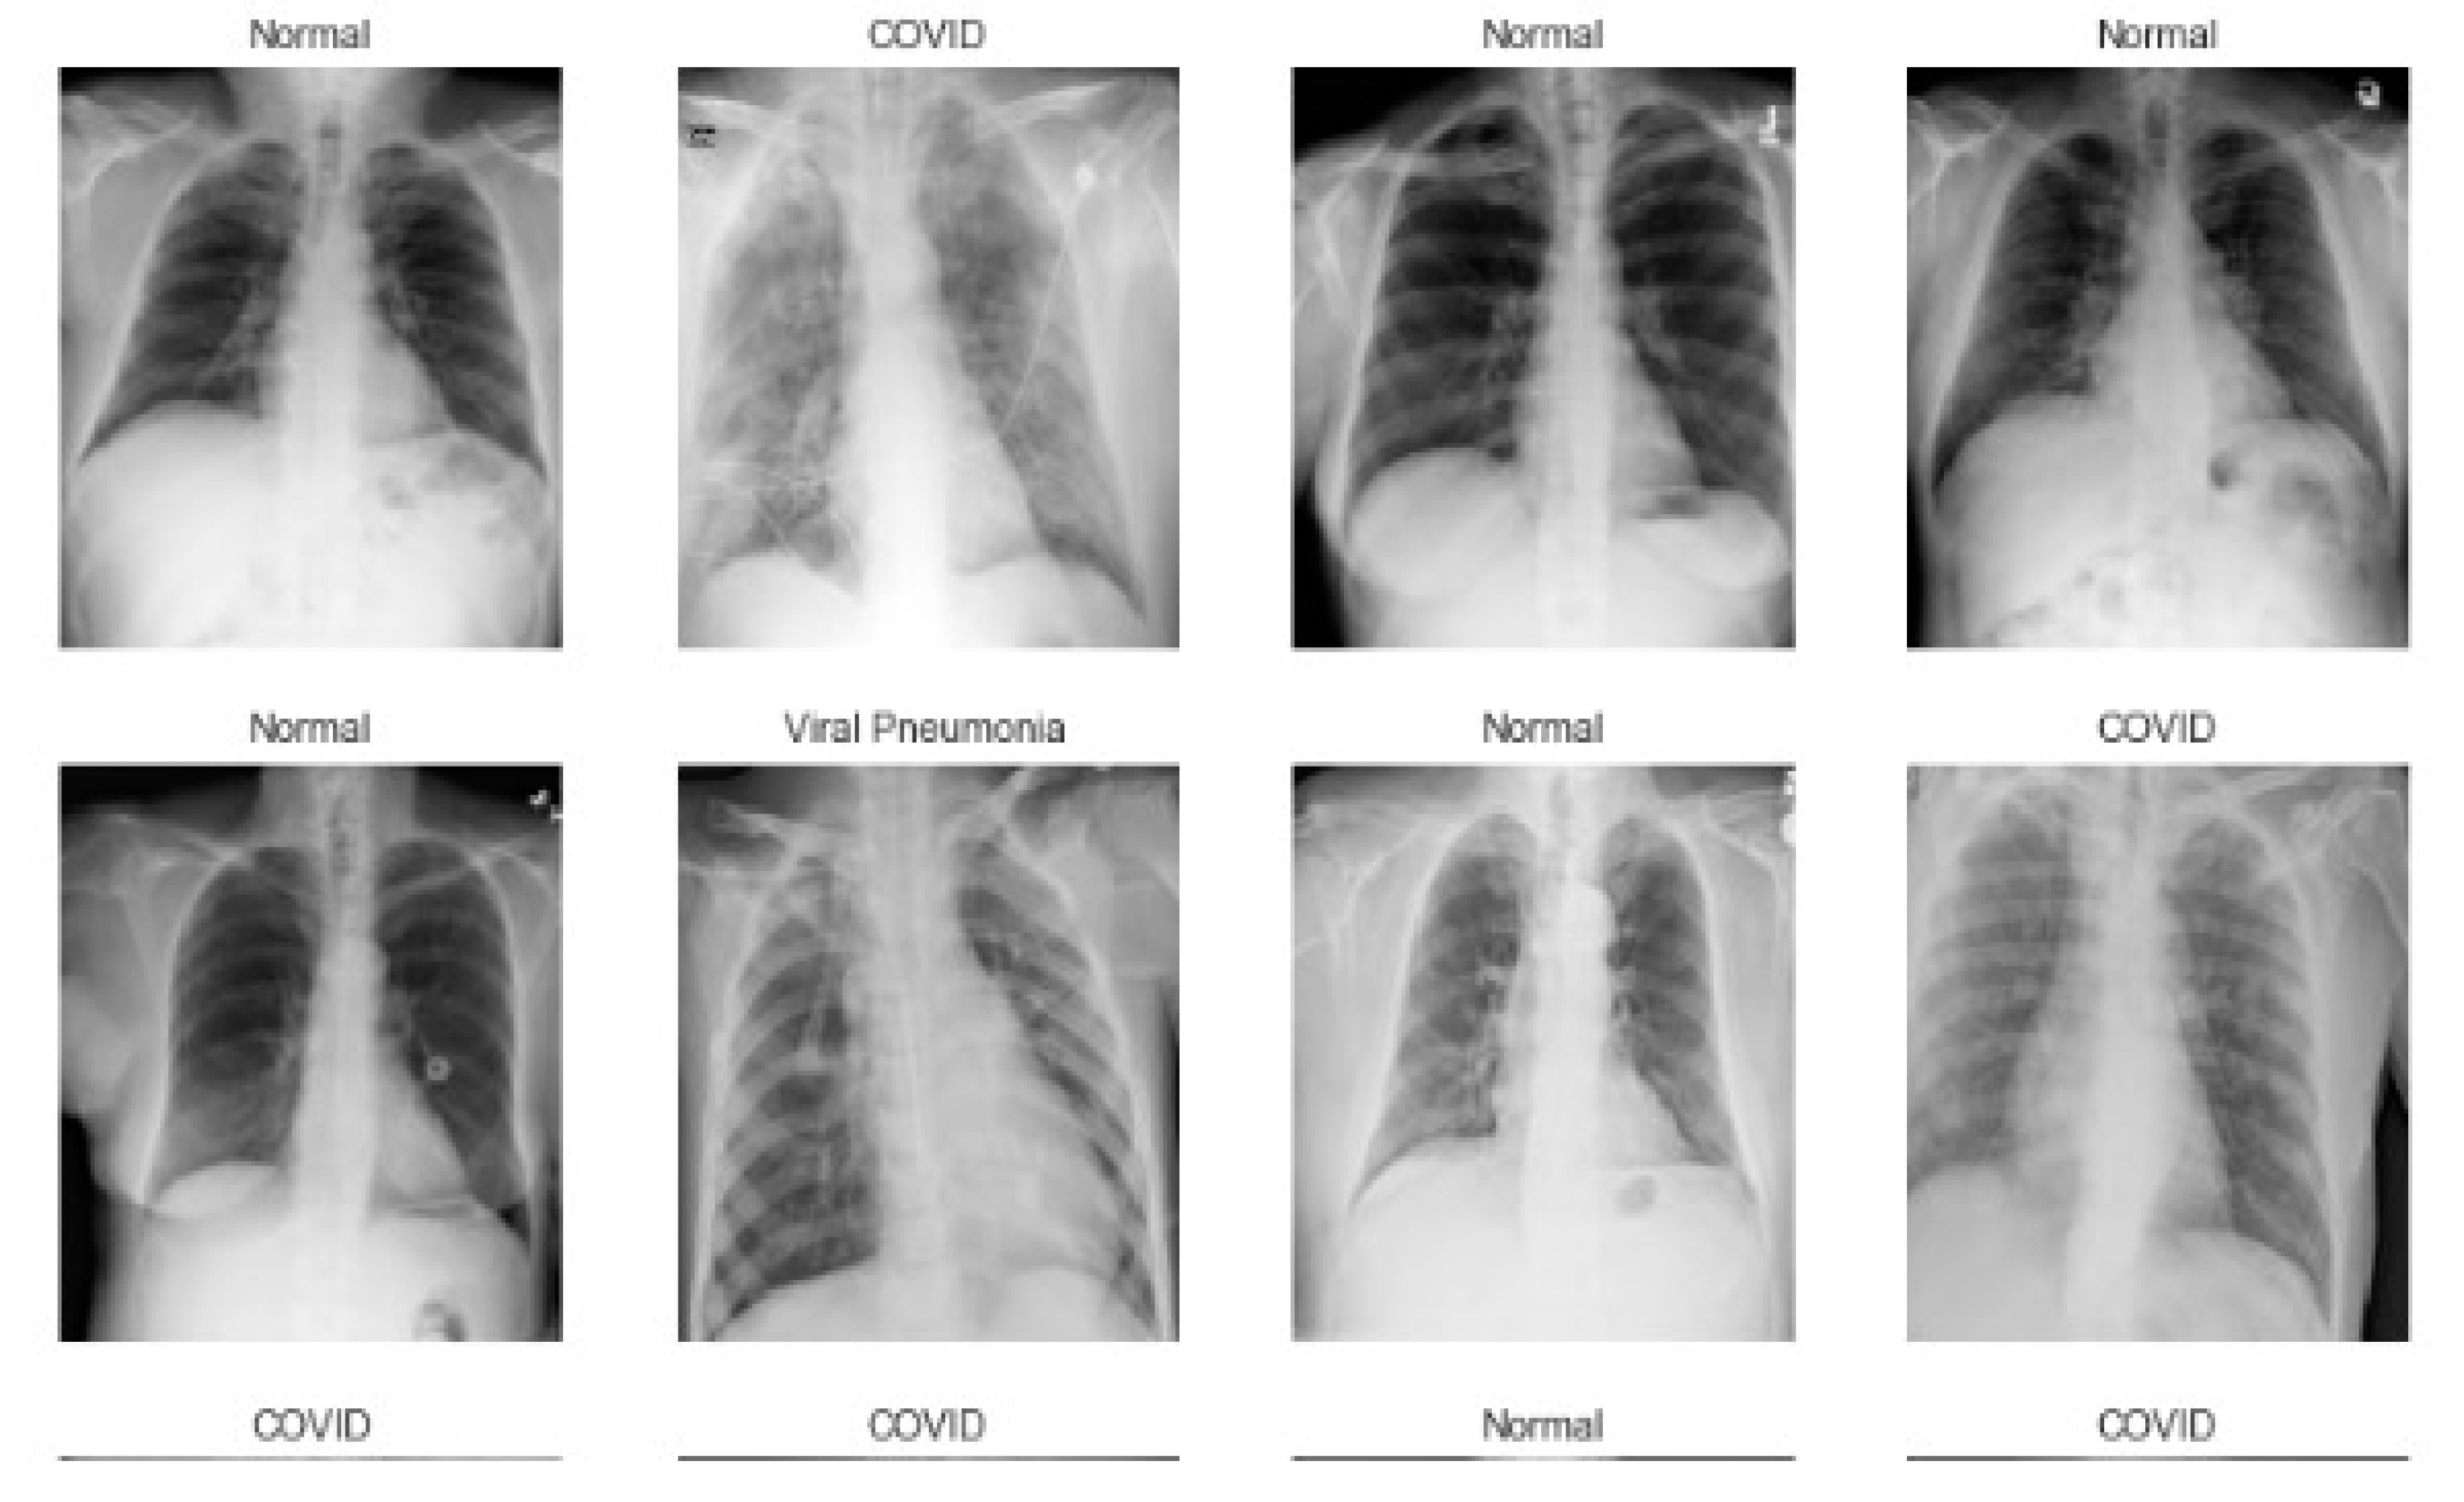

3. Chest X-ray Databases

| Symbol | Database | Normal | COVID-19 | Pneumonia | Lung Opacity | Total |

| Db1 | COVID-19 Radiography | 10,192 images | 3616 images | 1345 images | 6012 images | 21,165 images |

| Db2 | COVID-19 + PNEUMONIA + NORMAL Chest X-ray Images | 1802 images | 1626 images | 1800 images | - | 5226 images |

| Db3 | Chest X-ray (COVID-19 & Pneumonia) | 1583 images | 576 images | 4273 images | - | 6432 images |